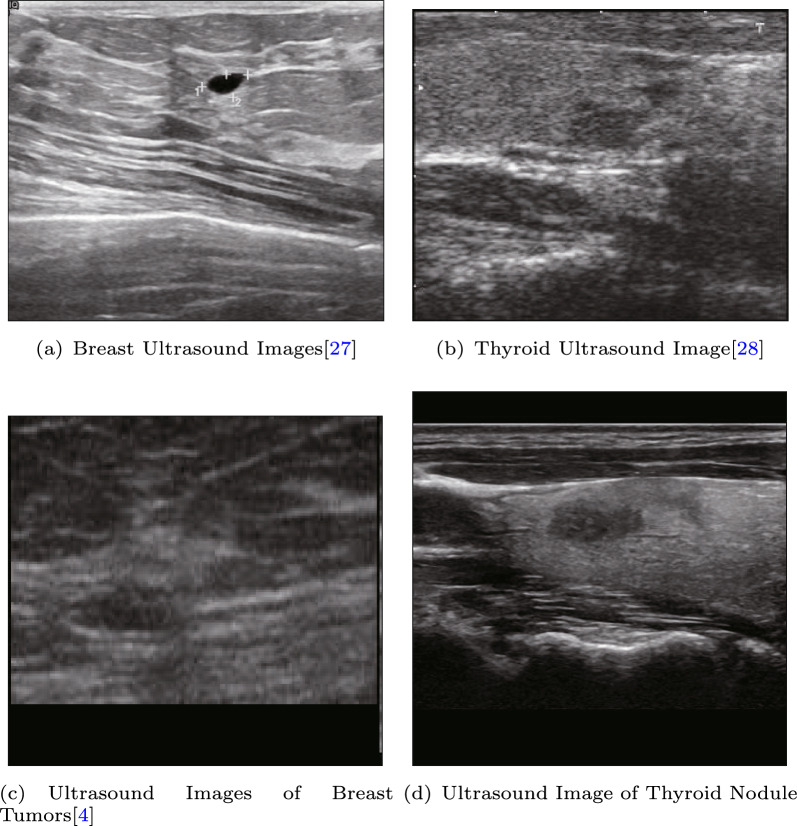

For public datasets, we utilized two ultrasound datasets: BUSI [27], which is a widely used breast cancer ultrasound dataset [28], and DDTI [4], which is a thyroid ultrasound dataset used for segmentation tasks, as shown in Fig. 9. Since there were no pathological results provided in these datasets, we used them for the puzzle pretext task. The aim of the pre-training phase was to enable the model to extract texture features related to ultrasound, and thus, the accuracy of the classification results during pre-training was not analyzed extensively.

Fig. 9.

Dataset for self-supervised pre-training